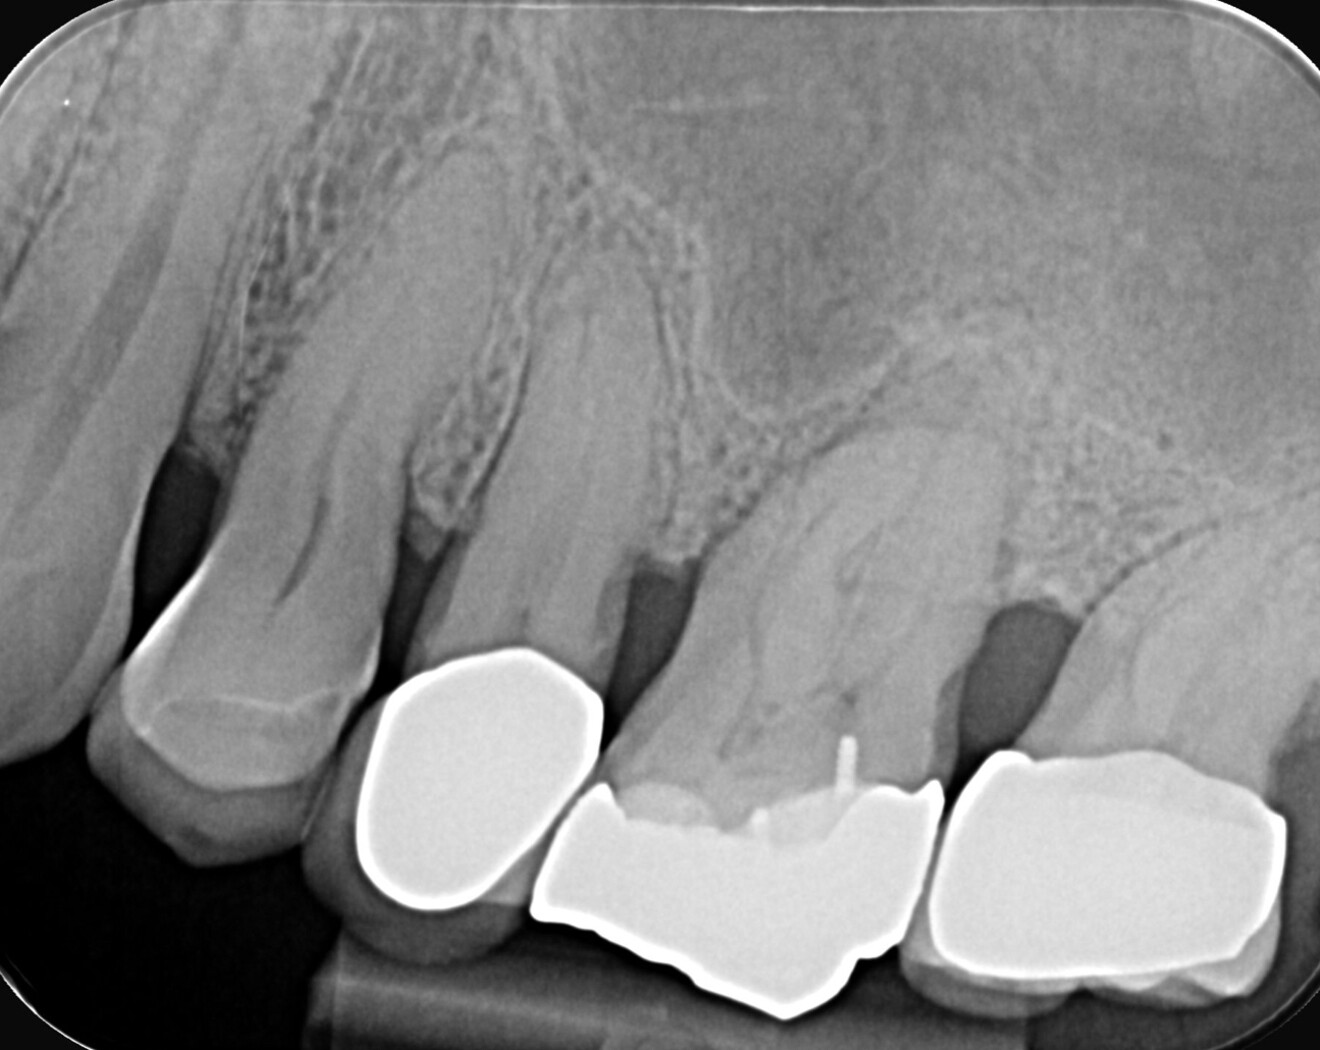

A patient with a periodontal issue was referred for the treatment of a maxillary and a mandibular molar. The maxillary molar was necrotic, and the preoperative radiograph showed a severely calcified pulp chamber and blocked root canal entrances (Fig. 7).

After creation of an access cavity, ultrasonic inserts were used at medium power with a non-diamond tip, to vibrate the calcification and remove it. Later, a diamond tip was used to adjust the access cavity and to give direct access to the canals. In this case, I chose to use Adaptive Motion in a single-file technique because the canals were curved and narrow. In such cases, it is better to start with a manual #8 and 10 K-file in order to feel the anatomy and check the working length. The first file was the 13/0.06 Traverse file (Kerr Dental), used in a pecking motion for 3 seconds, taking it out, cleaning it and rinsing the canal until the file reached the working length. Sometimes, this method takes a single pass or several, depending on the anatomy. This pre-shaping file was followed by the 20/0.06 ZenFlex file and later by the 25/0.06 ZenFlex file to working length. A full irrigation sequence was used, followed by 3D vertical obturation (Fig. 8).

The mandibular molar too was necrotic and presented with internal calcification. This is the result of the chronic activation of inflammatory pathways in the body, which can lead to the formation of micro blood vessels within the pulp that later calcify as a defensive response to slow, chronic aggression. This kind of calcification can cause irreversible pulpitis and later necrosis of the pulp. In this case, the calcification could clearly be seen all along the root canal system, reaching almost to the apical area (Fig. 9).

Fig. 7: Pre-op radiograph showing a maxillary first molar with a very calcified pulp chamber and narrow canals.

Fig. 9: Pre-op radiograph showing calcification along the entire length of the canals.